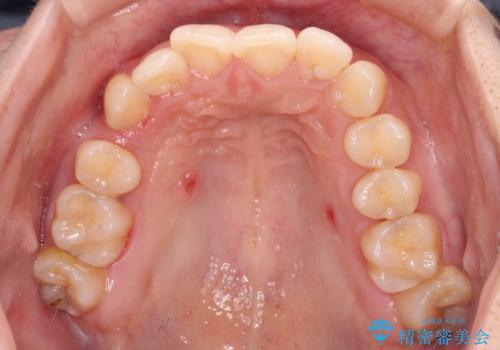

八重歯の抜歯矯正 補助装置とワイヤーを併用したインビザライン矯正治療

- 八重歯と上顎正中のズレを気にして来院された患者様です。

インビザラインによる矯正治療を希望されたため、八重歯改善のための抜歯矯正部分や上顎正中の大幅に位置移動は、補助装置やワイヤー矯正を併用し、その後はインビザラインにて行うこととしました。

骨格的に下顎が左側に変位していたため、上下正中を合わせることは困難であることは分かっていましたが、可能な限り合わせることができました。

骨格的なズレがあると仕上げの段階で奥歯の咬み合わせが不安定となるため、予定よりやや長期間となりました。